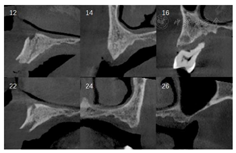

影像学检查:曲面体层片及根尖片示13、16、42、38、48牙槽骨吸收至根尖;剩余牙牙槽骨吸收至根长1/2。CBCT示上颌正中多生牙,多生牙舌侧可见不规则低密度影像。(图2、图3)

术前CBCT检查上颌骨量显示,12 mm>前牙区骨高度≥8 mm,骨宽度<6 mm;12 mm>右侧后牙区骨高度≥8 mm;左侧后牙区骨高度<4 mm,骨宽度<6 mm。依据Carames[9]全牙列综合种植解决方案分类,属于复杂种植方案设计,如全牙列行种植后固定义齿修复,需设计6颗种植体。种植体设计有4种方案,其中3种方案涉及到2颗斜形种植体在上颌窦前侧壁的种植及后牙区的穿颧或穿翼种植;另一种种植方案是双侧后牙区骨增量,左右各种植3颗种植体,本病例6颗种植体的设计方案与上述解决方案一致,所不同的是在导板定位的情况下利用了前牙区、前磨牙区及右侧后牙区的有效骨量轴向种植5颗种植体,因左侧后牙区颊侧骨壁吸收多,该区骨宽度及高度均不足,因此在种植同期对左侧后牙区实施了上颌窦侧壁开窗提升植骨技术,术后6个月在左侧后牙区轴向植入1颗种植体,规避了双侧上颌窦前侧壁区斜形种植及双侧后牙区穿颧及穿翼种植,降低了手术难度及风险,患者接受度高。